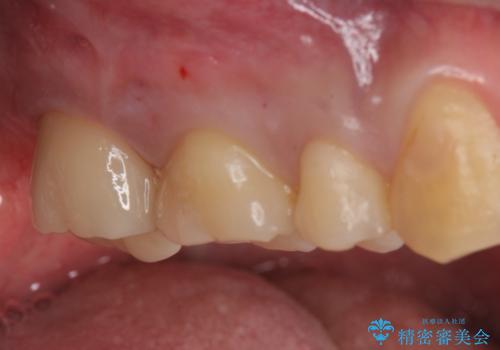

- 一番奥の銀の詰め物を白くしたいとのことで来院。

セラミックの詰め物のやりかえだと範囲が多く、割れてしまうリスクがあります。

そのため、割れるリスクが少ない詰め物ではなく、被せ物による治療(ジルコニアクラウン)を行いました。

また、隣の歯も白い樹脂の下が虫歯になっており、セラミックの詰め物(e-maxインレー)による修復をしました。

白い被せ物が入り希望に沿った処置となり

大変満足して頂けました。